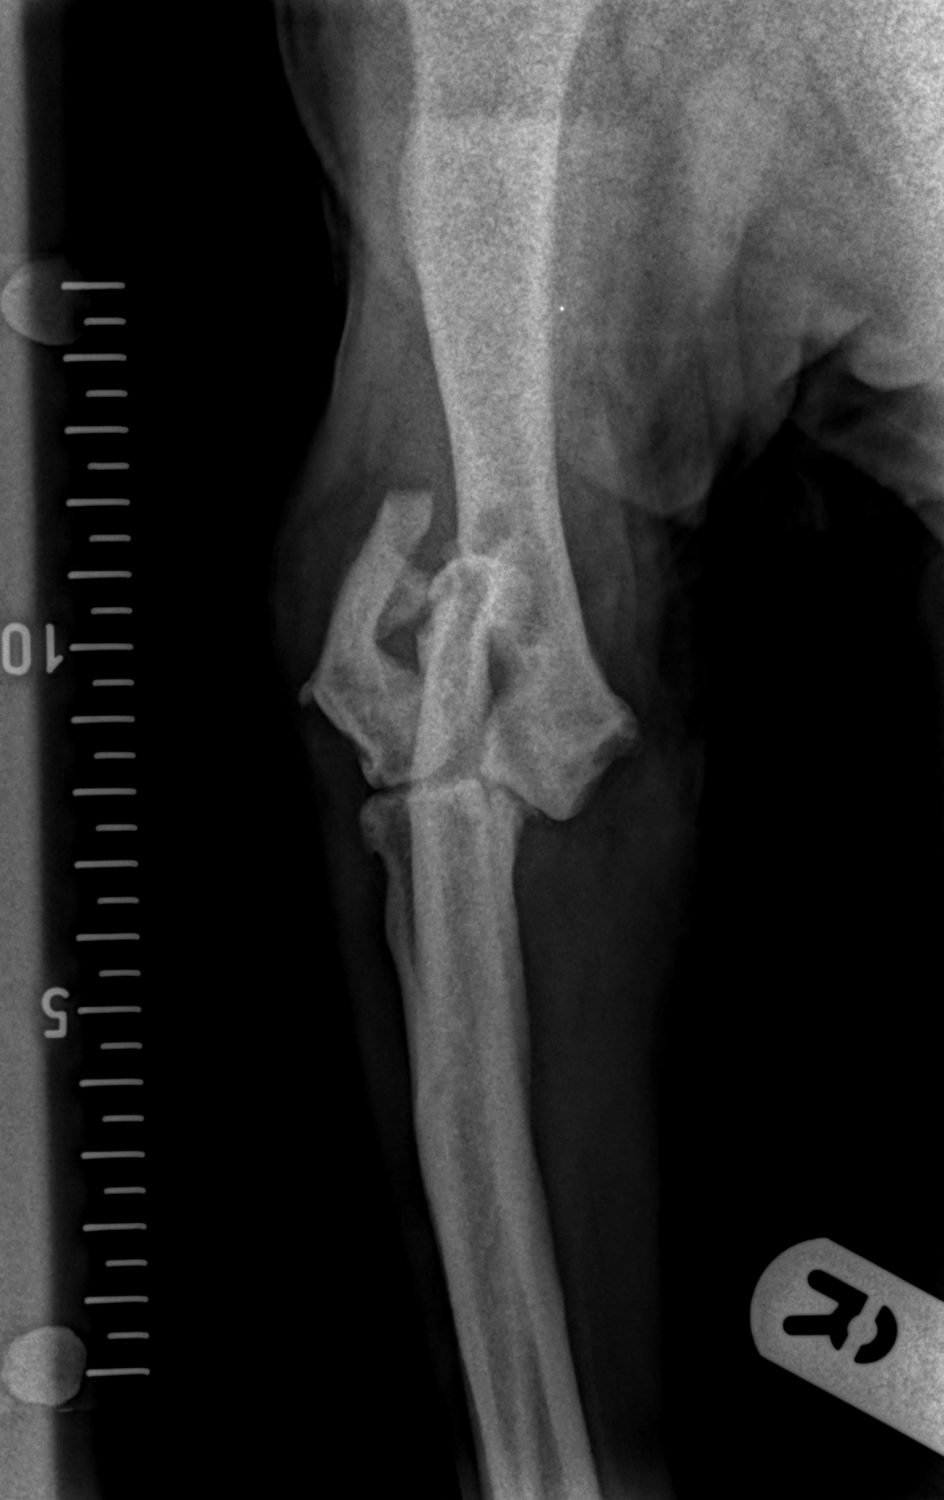

Chase is a  twelve-year-old English Springer Spaniel, with a history of severe arthritis in his elbows, presented lame in the right elbow after sustaining an injury whilst jumping into the car. X-rays revealed a humeral intracondylar fissure that had fractured.

A humeral intracondylar fissure is a crack within the joint of the elbow; this weakens the joint and significantly increases the chance of fracture. It can affect many breeds but is especially common in English Springer Spaniels.